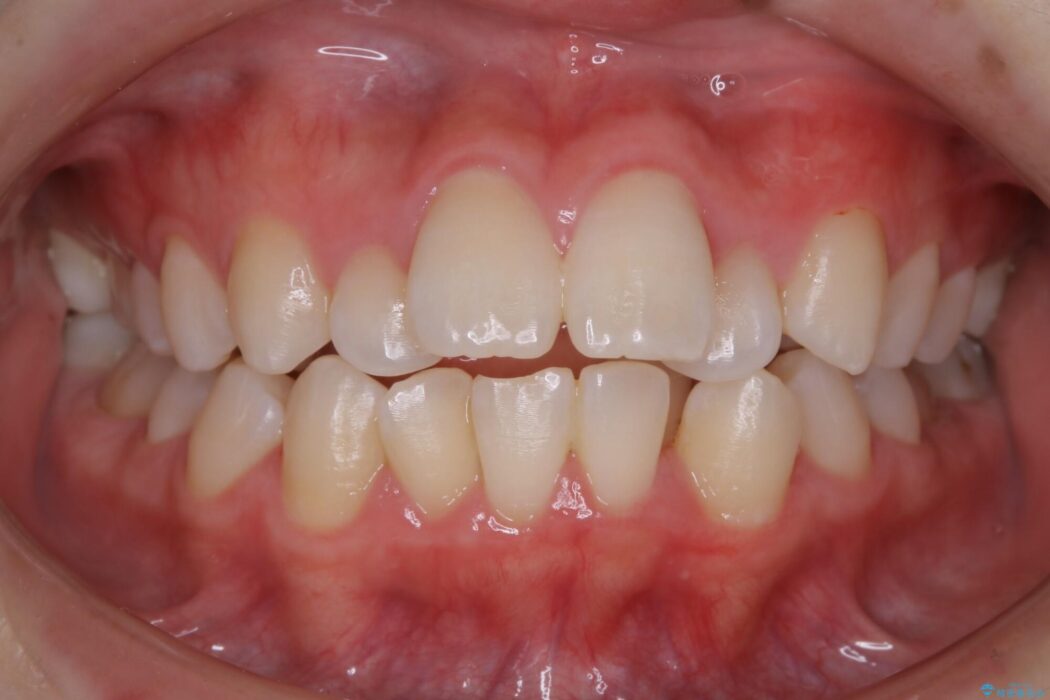

前に出ている口元を下げたいとの主訴で来院されました。

検査したところ歯に対して骨が上顎・下顎共に小さいことがわかりました。

それによりスペースが少なく歯列がガタついたり前方傾斜する生え方となっていました。

本症例の患者様は顎の骨が小さく歯をきれいに並べるための隙間がないため、歯が重なったり傾斜してしまっていました。